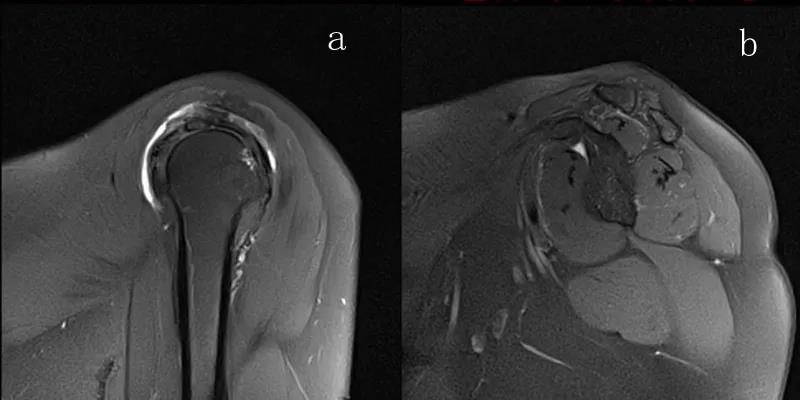

图21 斜冠状位(临床常用)a.T2,b.T1

图22 斜矢状位 a.冈上肌出口,肩袖诊断不如斜冠状位;b.冈上肌及肌腹脂肪浸润成度,评估手术与否

图23 横断位a.正常肩胛下肌;b.肩胛下肌损伤

图24 a.肩袖全层撕裂;b.正常MRI

2、MRI检查MRI目前是诊断肩袖疾病中最常用的检查,可以直观的观察肩袖肌腱。